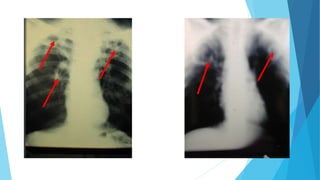

 Infiltrados pulmonares múltiples

en la mitad inferior de ambos

campos pulmonares.

Imagenología

 Infiltrados pulmonares bilaterales

en los campos medios,

superpuestos a los hilios.

 Infiltrado pulmonar unilateral

basal derecho